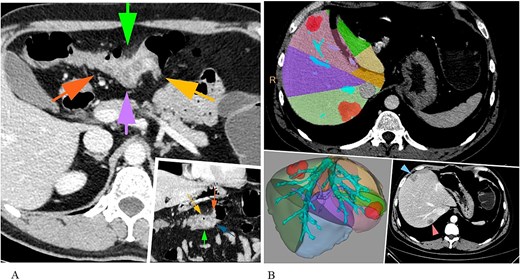

Liver surgery was conducted as a first surgical stage with application of Ligasure Maryland and ultrasonic cavitation device. The patient was positioned in the modified left jack-knife position (Fig. 2). The trocars were placed according to the technique described by Y. Okuda with 5 mm trocar in ninth intercostal space [6]. We used the intracorporeal intermittent Pringle manoeuvre technique according to Jian-Wei Huang for in-flow blood control [7]. Liver mobilization included transection of the right triangular, and falciform ligaments with patrial ‘piggy-back’ manoeuvre. 14 Fr Foley catheter was placed as a tourniquet on the right hepatic vein (RHV) to control the outflow (Video).

Patient's positioning on the operating table (modified left Jack-knife position) during liver resection. A 5-mm trocar was placed next to the xiphoid process, and the other two 12-mm trocars were placed at intervals of 6 cm next to the 5-mm trocar. The intercostal 5 mm trocar was placed through the ninth intercostal space on the right posterior axillary line.